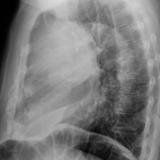

Case 2

Thymoma